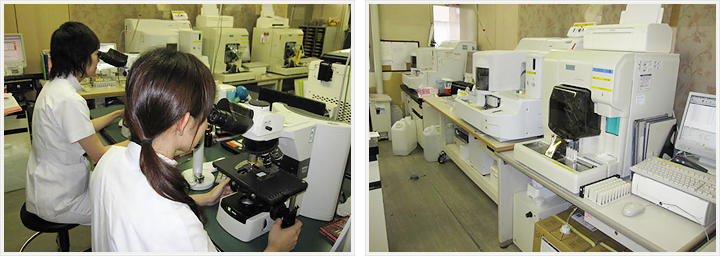

検体検査部門

分析部門

夜間・休日を含めた24時間体制にて、信頼性の高い検査データを迅速に報告しています。一部の検査を除き検体到着後60分以内で結果報告する体制をとっています。

血液検査

血球計算、血液像検査、凝固線溶検査、骨髄像検査を実施しています。

血液像検査は標本を作製し、鏡検により白血球分類を行っています。

一般検査

尿定性・沈渣、髄液検査、便検査、穿刺液検査を行っています。